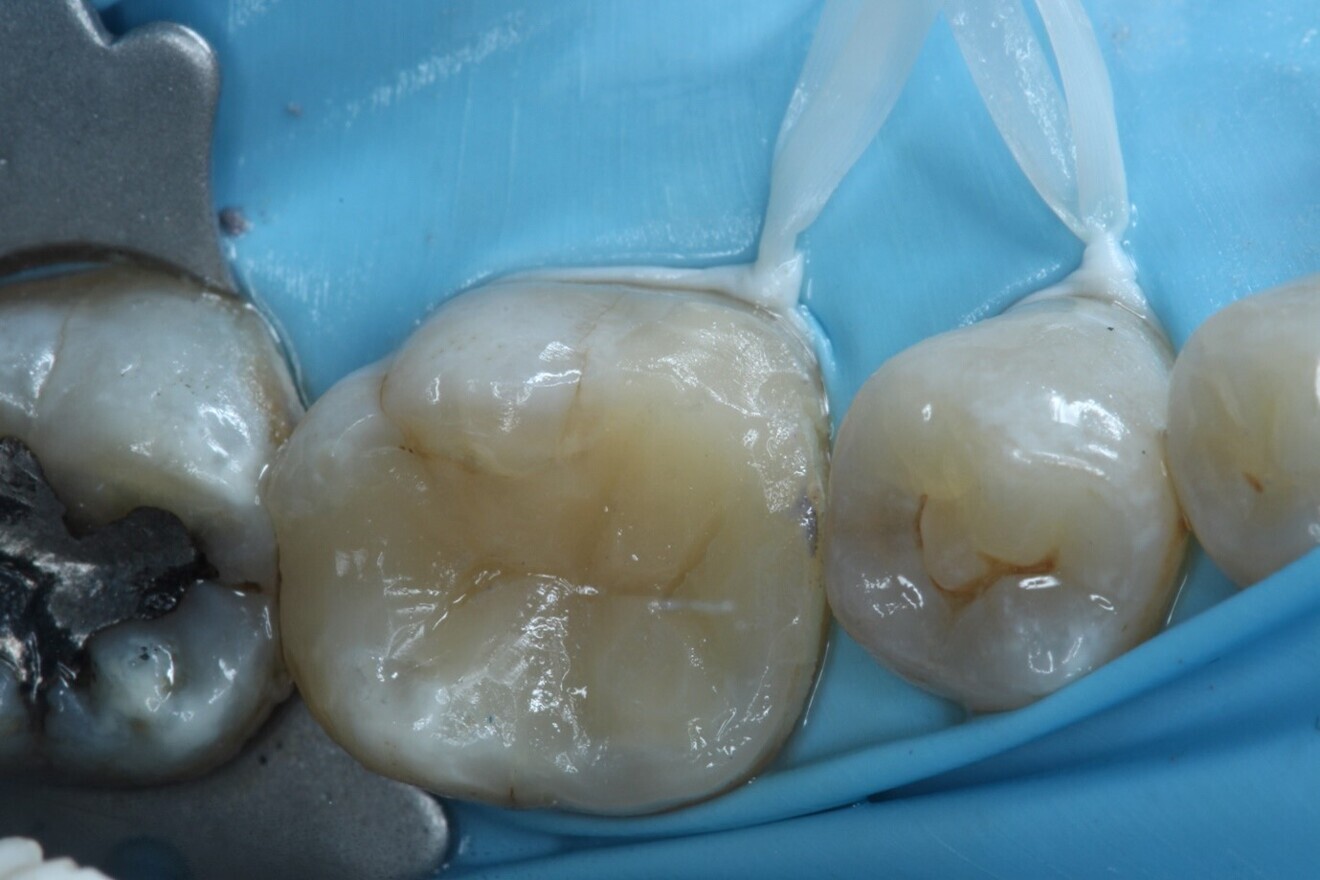

Fig. 7: After deep marginal elevation and restoration of the marginal ridges of tooth #36.

Fig. 8: Interim glass ionomer cement restoration placed to allow re-establishing of access to the canals at the next visit.

The canals were dried with paper points, a calcium hydroxide paste was placed in the canals and PTFE tape was used in the pulp chamber space. In order to improve the fracture resistance of the tooth in between appointments, deep marginal elevation was carried out with composite for the mesial marginal ridge, utilising a band-in-band technique. The tooth was temporarily restored with a glass ionomer cement, and the occlusion and contacts checked (Figs. 6–8).